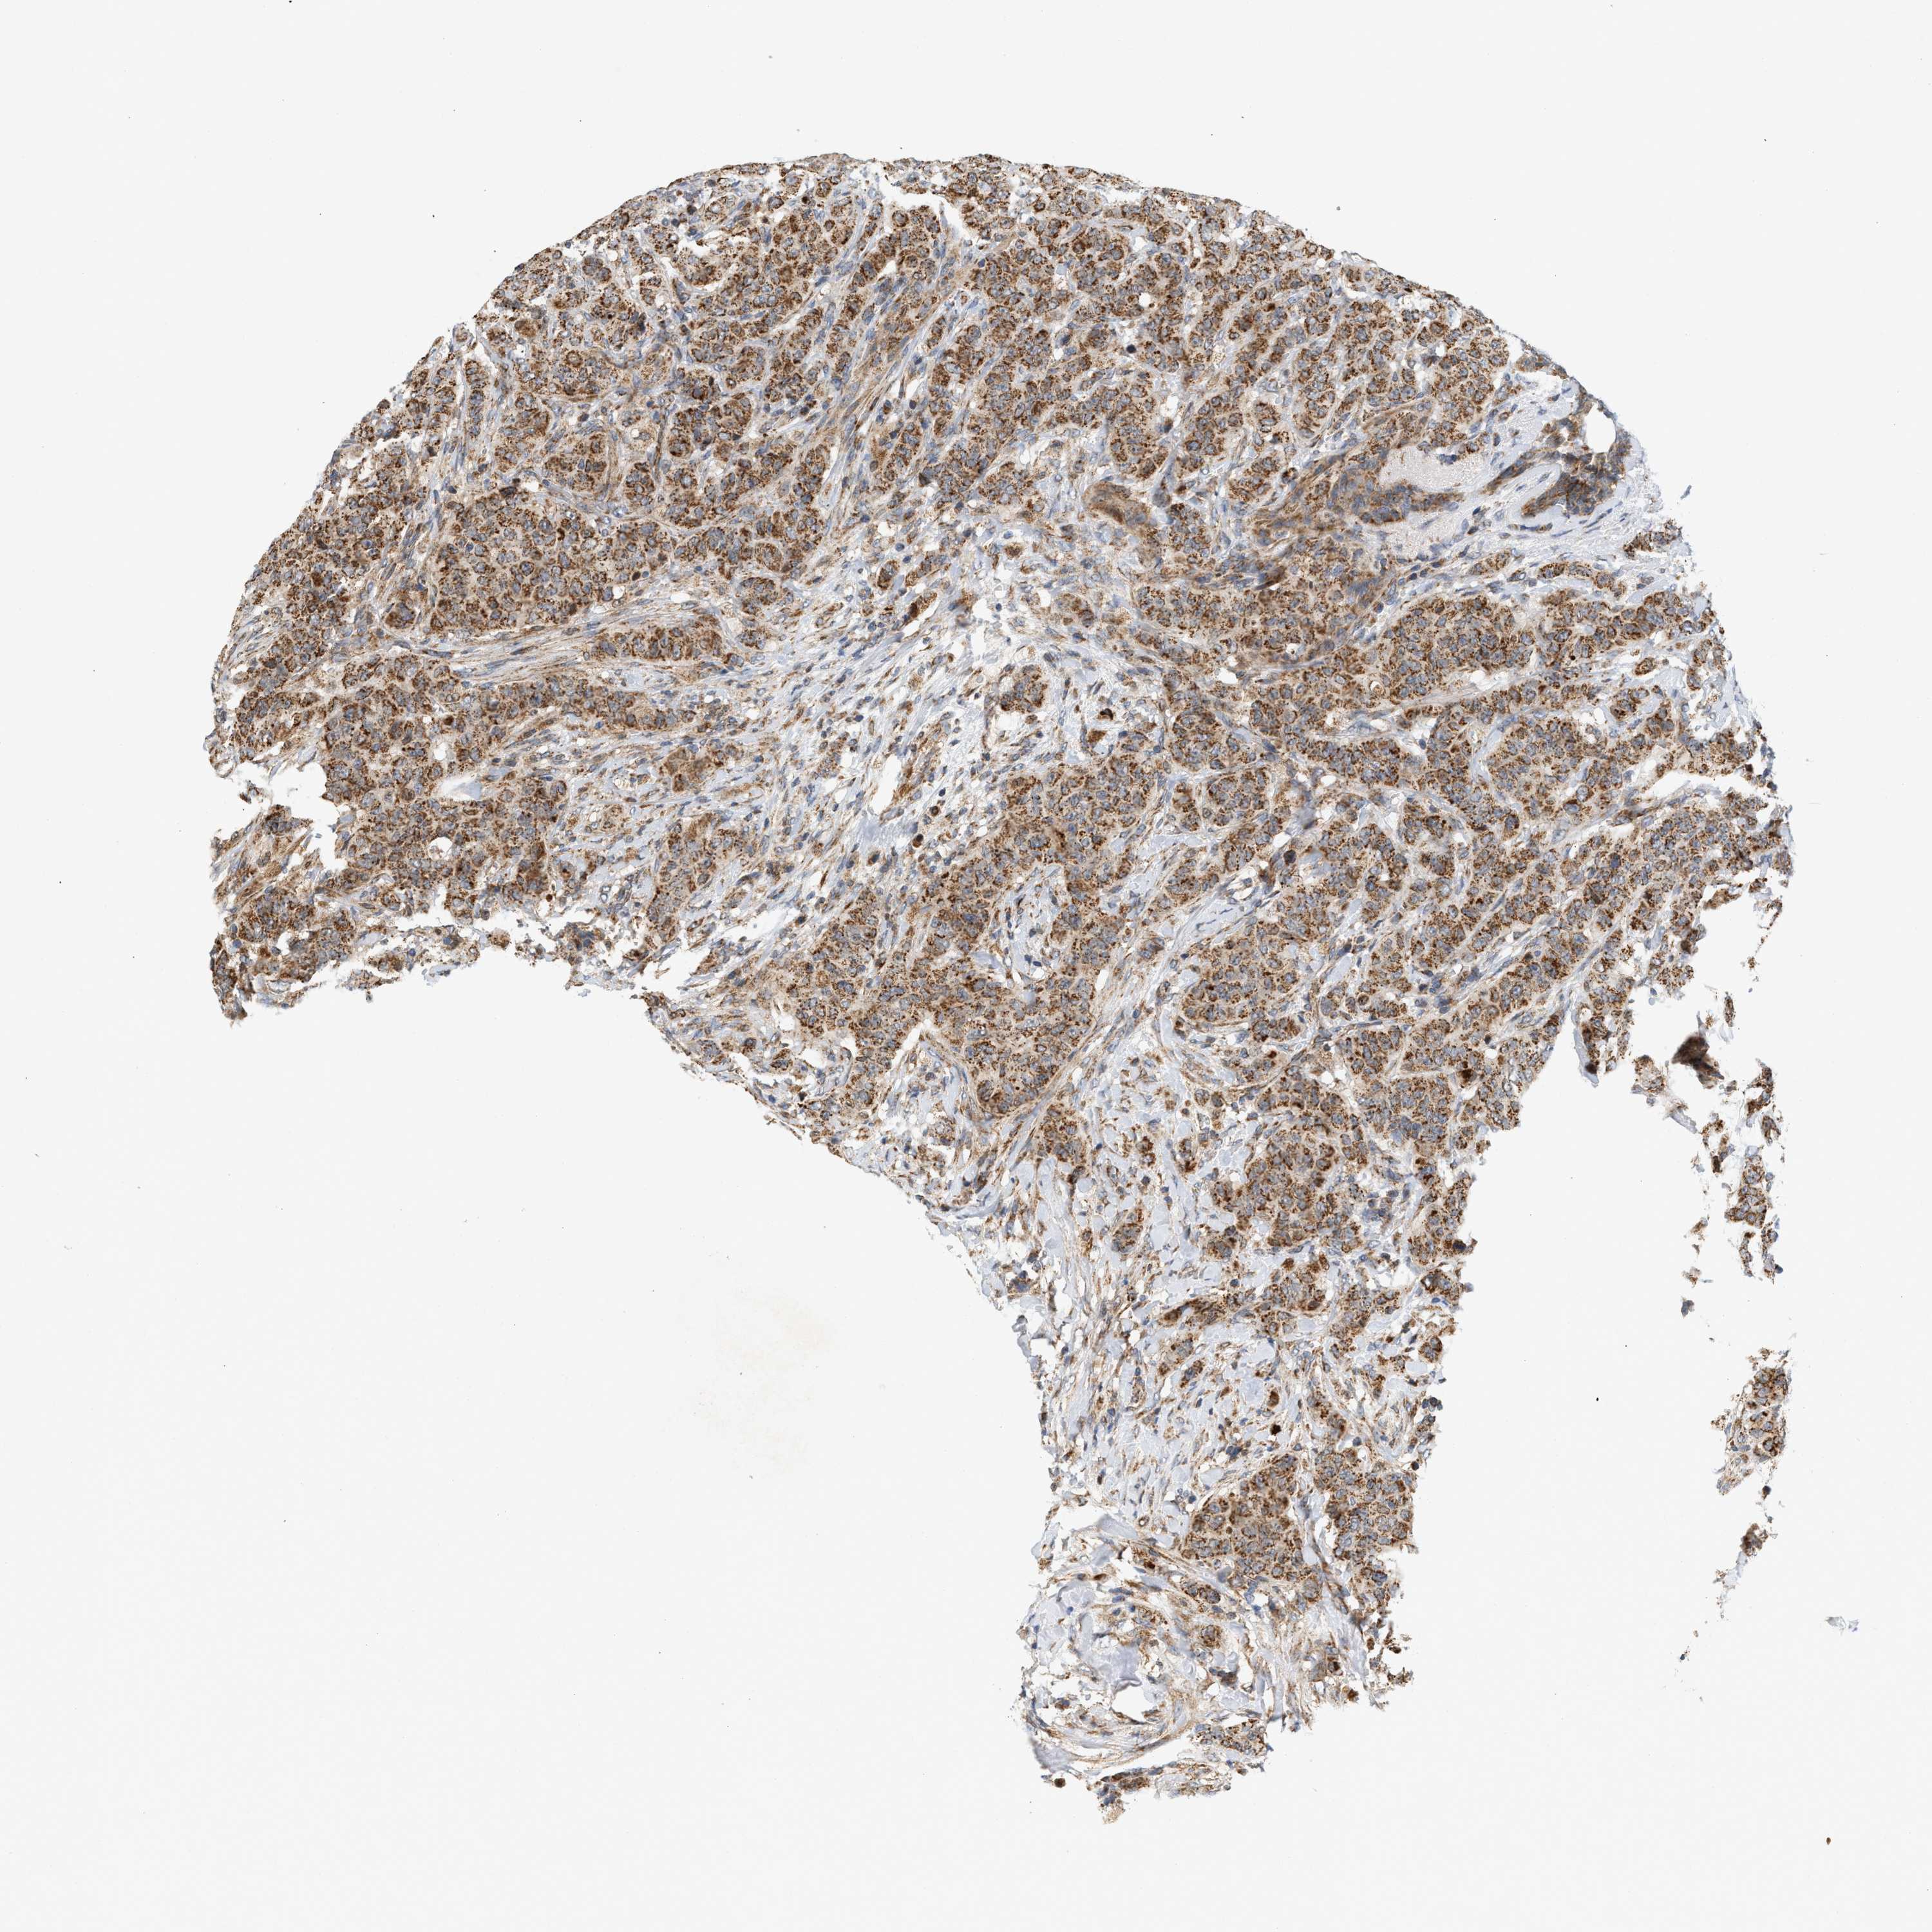

CANCER BREAST CANCER Show tissue menu

BRCA TCGA BRCA VALIDATION PROTEIN EXPRESSION